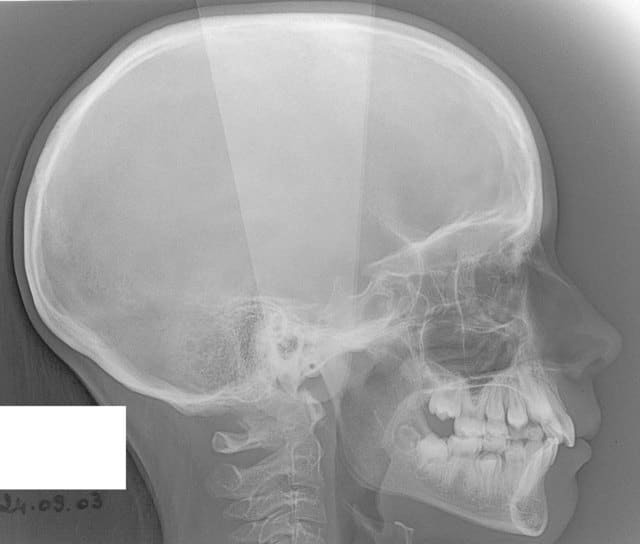

chakour

22/05/2008 à 00h10

début 2008,quadhélix en 0.28,pour vestibuler la 2,ce qui est fait

Tele2002 qhiepn - Eugenol

Tele2007 b6yul0 - Eugenol